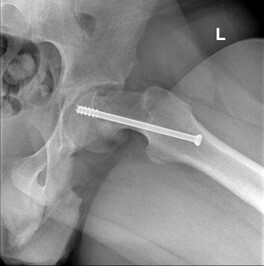

- Fissazione in situ. Questa è la tecnica utilizzata più spesso per i pazienti con epifisiolisi stabile o lieve. Mediante una piccola incisione chirurgica si inserisce una vite metallica attraverso la cartilagine di accrescimento (fisi) per mantenere la posizione della testa del femore e prevenire altri scivolamenti (fig. B). Nel tempo, la fisi si chiuderà. Una volta che la fisi è chiusa, non si possono verificare scivolamenti;

Fig B Fissazione della testa del femore con l’utilizzo di una vite.